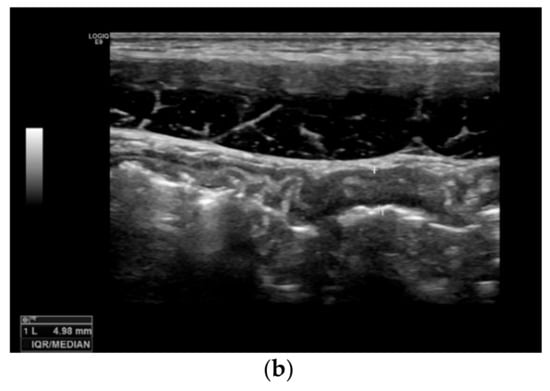

Bowel wall thickening (BWT): this parameter measures the distance from the interface between the lumen and the mucosa layer and the interface between the serosa layer and the proper muscle. It should be measured in the anterior wall of the bowel (or where it is better visible) in the longitudinal direction, avoiding haustrations and mucosal folds (see Figure 2) []. Bowel wall thickening is the most important and most used IUS parameter for the diagnosis of CD []. A cut-off value of 3 mm has shown a sensitivity and specificity of 89% and 96%, respectively. A cut-off value of 4 mm or more showed a sensitivity of 87% and a specificity of 98% [].

Figure 2.

Measurement of bowel wall thickening and bowel wall stratification: Bowel wall thickening is the most important IUS parameter in IBD patients. The most commonly used cut-off value is 3 mm. The bowel wall stratification can be focally or extensively disrupted or lost due to inflammation. (a) Bowel wall thickening with preserved layer stratification. (b) Bowel wall thickening with loss of stratification.

Bowel wall echo-pattern or bowel wall stratification (BWS): the bowel wall has a clearly defined multilayered aspect, but stratification can be focally or extensively disrupted or lost due to inflammation (see Figure 2). Disruption of stratification is associated to higher degrees of inflammation.